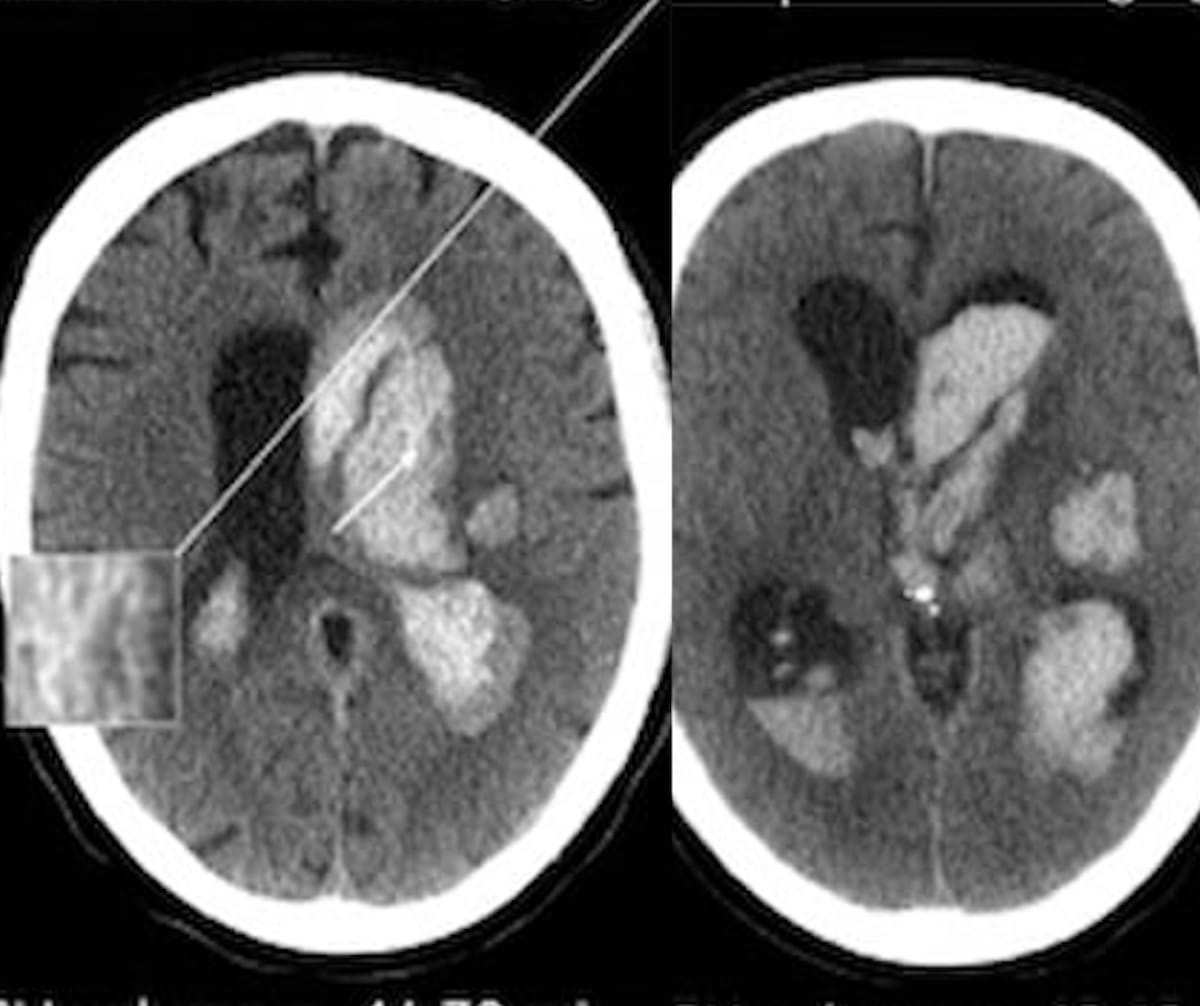

In a subgroup analysis of patients with intracerebral hemorrhage who had intraventicular hemorrhage (IVH) growth, researchers found that hypodensities on non-contrast computed tomography (CT) were associated with more than double the risk for greater than 1 mL of expanded IVH (eIVH).